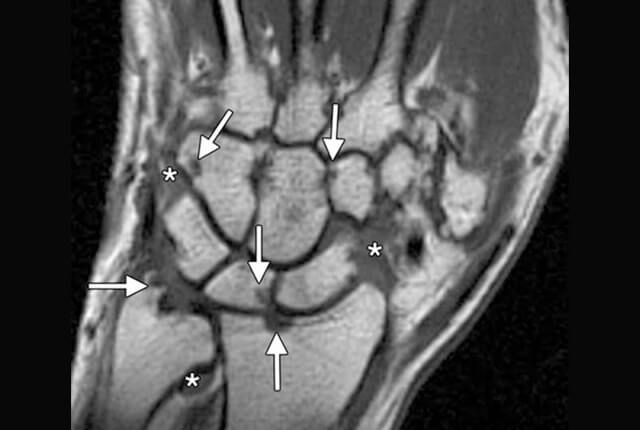

MRI:滑膜炎、骨びらん、関節破壊を早期に発見できます。当院ではオープン型MRIを完備しています。